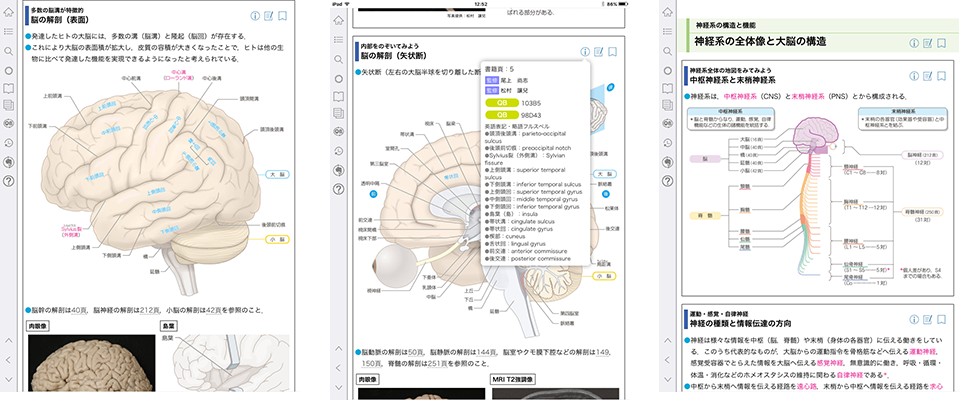

脳 脳幹 大脳 小脳 のしくみや働きがすぐわかる 高次脳機能障害の全て

脳画像におけるct Mriの見方 みるべきポイントさえ押さえれば 脳画像は簡単に見れる リハアイデア

脳画像の利用の仕方 For Pt Ot St

M2plus Pt Otのための 高次脳機能障害abc

動画解説 脳血管 動脈 の解剖を図と画像でわかりやすく

頭部mra 脳の血管 の解剖の基本 ポイントを動画付きで解説

脳画像の利用の仕方 For Pt Ot St